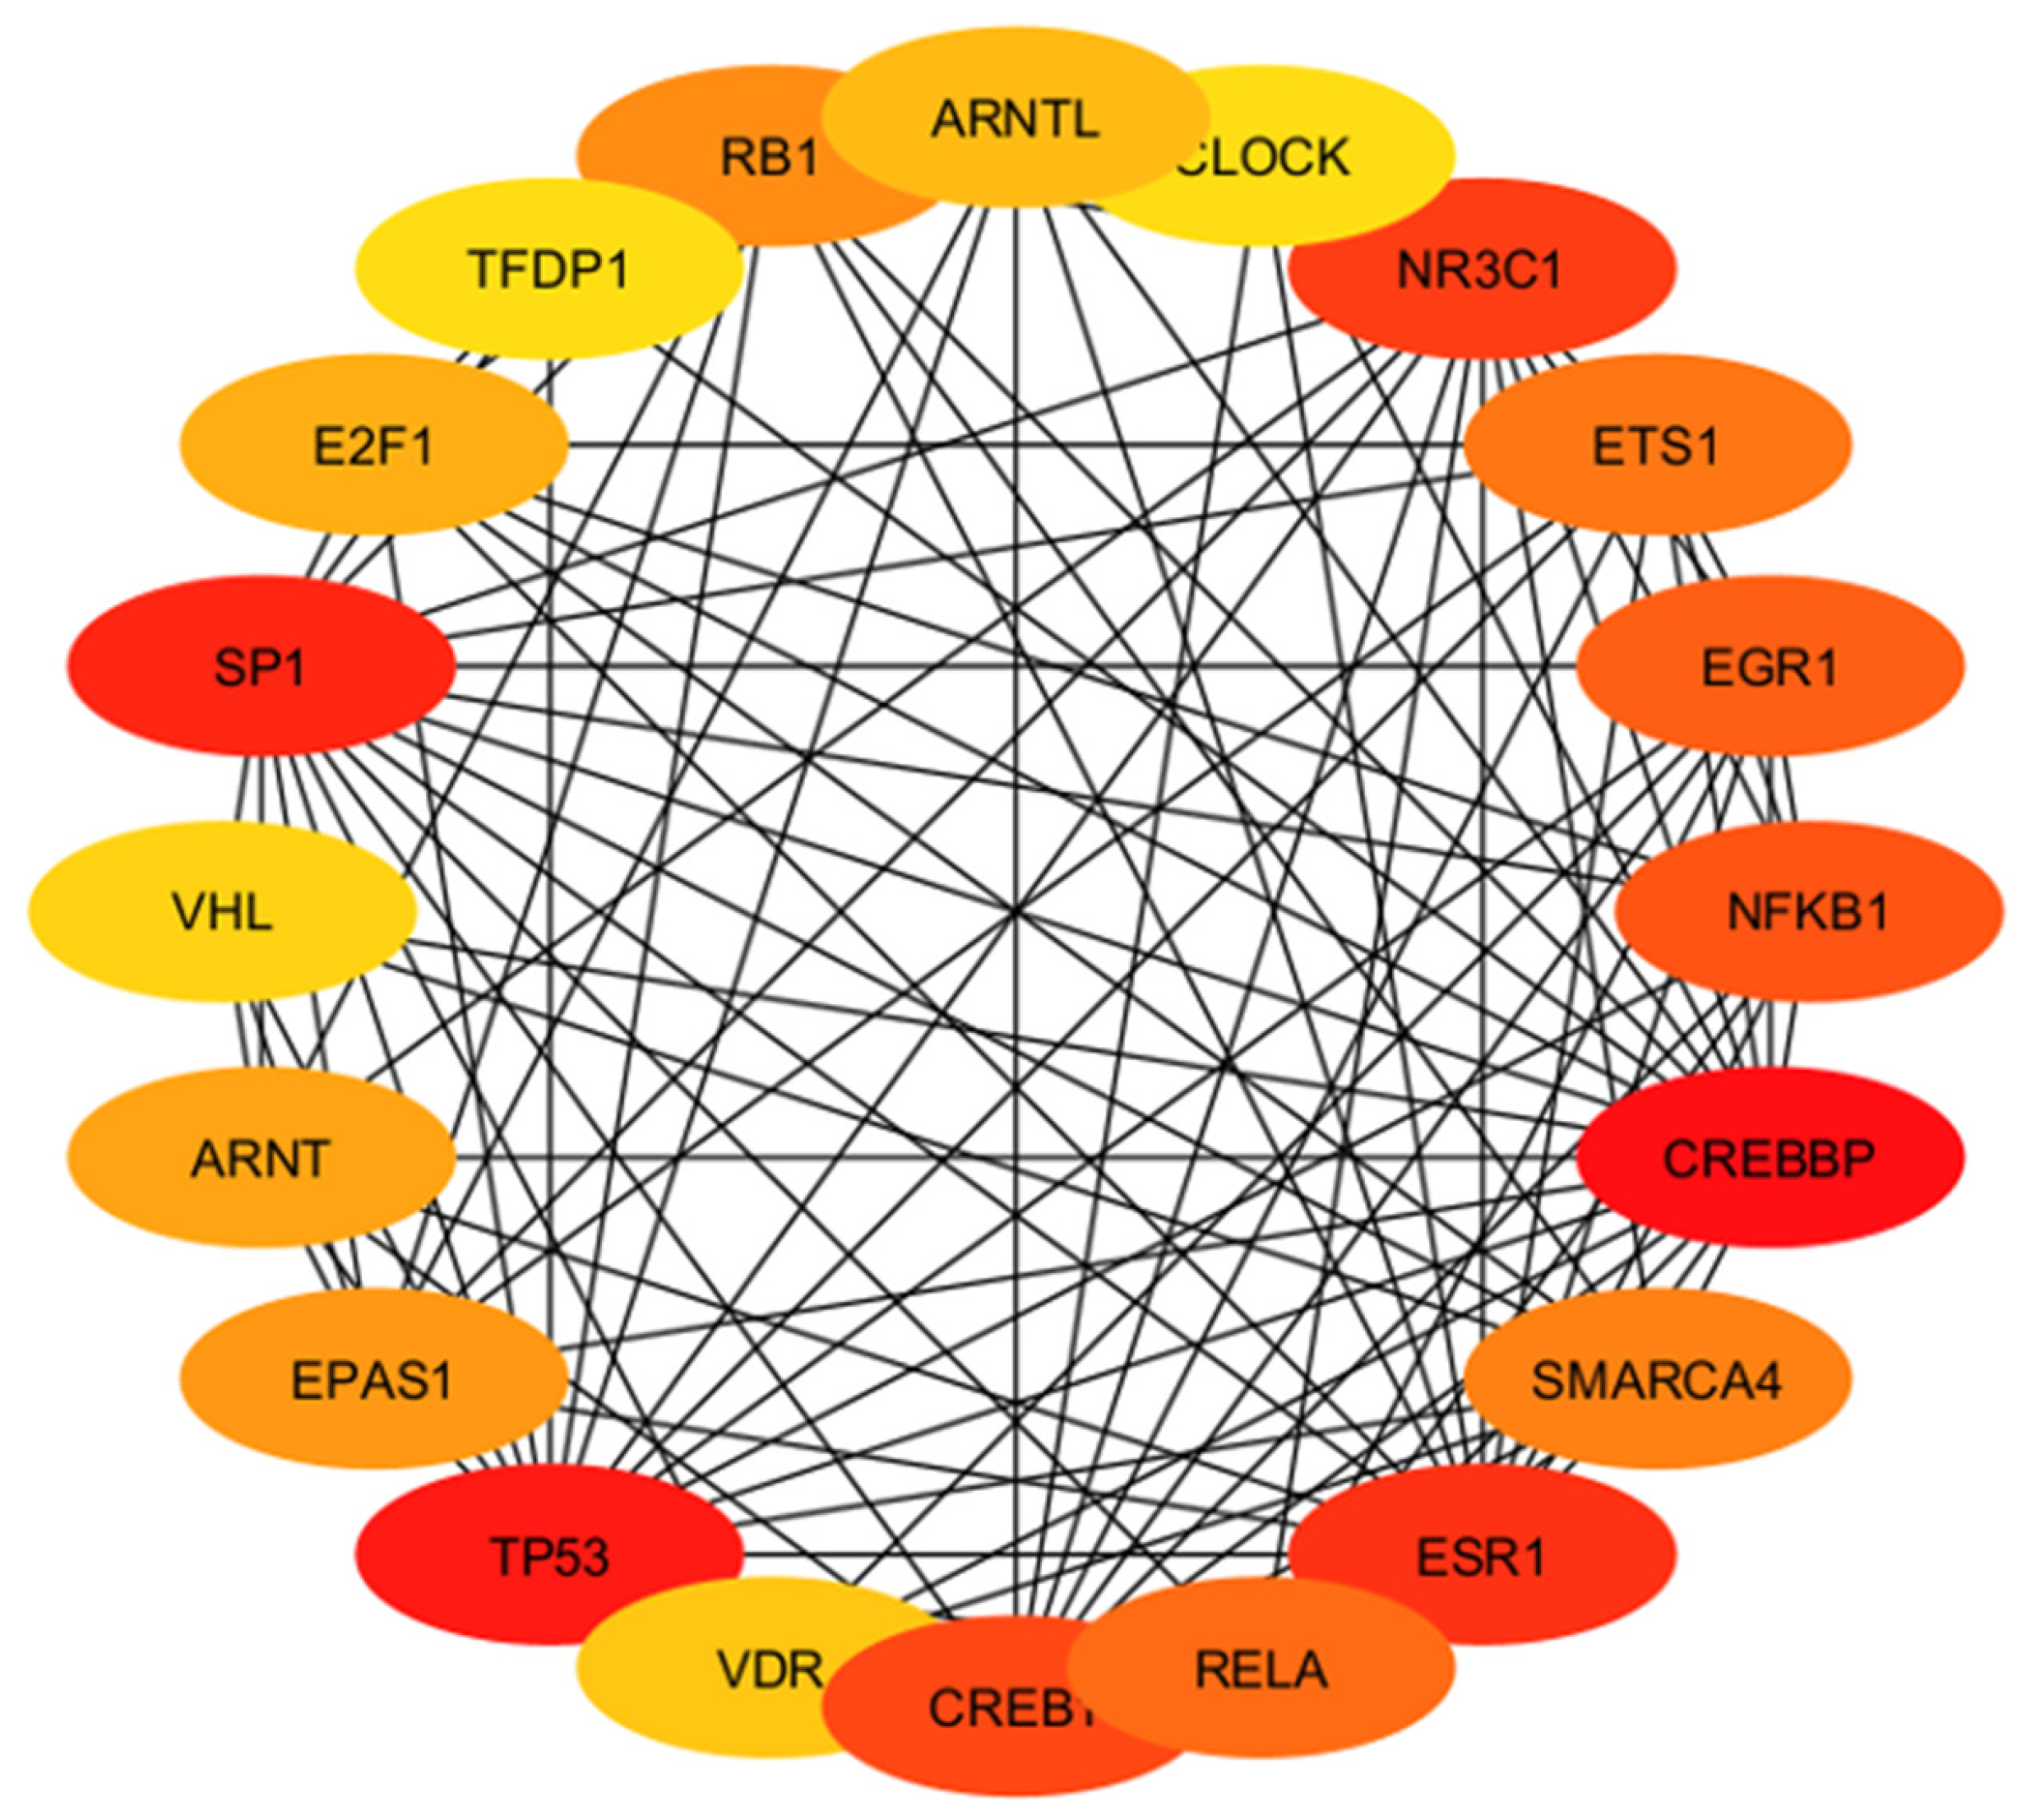

2.4.4. Identification and Analysis of Hub Gene

2.4.5. Gene Ontology and Functional Annotation Analysis of Hub Genes

3. Results

4. Discussion

4.4. Involvement of Hub Genes in Preeclampsia Development

4.5. Hub Genes with Diagnostic and Therapeutic Perspectives